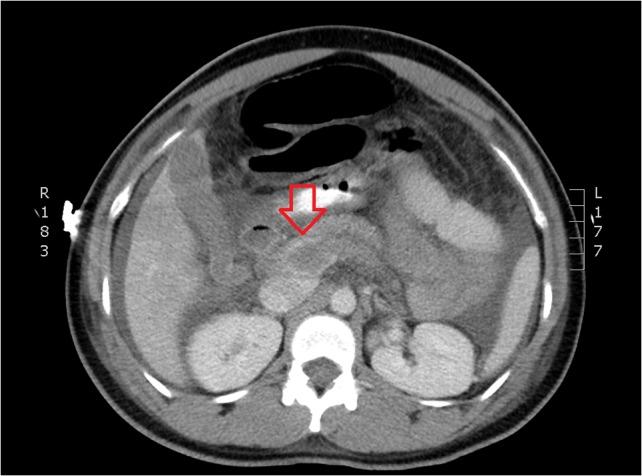

Portal vein thrombosis (PVT) has been recently documented after a variety of laparoscopic surgeries. Although it is well established in splenectomies, its prevalence in other laparoscopic procedures is rare. PVT in colectomies has been associated with inflammatory processes, such as ulcerative colitis and diverticulitis. We report a case of postoperative PVT following a total abdominal colectomy for colonic inertia. A 27-year-old female underwent an uneventful elective laparoscopic total colectomy with ileorectal anastomosis for colonic inertia, and presented on postoperative day (POD) 3 with obstipation, abdominal distention and emesis. Her abdominal pain increased on POD 4 and computed tomography revealed PVT. PVT following laparoscopic surgery is rare in cases not involving the spleen. Although previously seen in colectomies for inflammatory conditions, it can present after colonic inertia. A high index of suspicion should be maintained to diagnosis this rare complication.